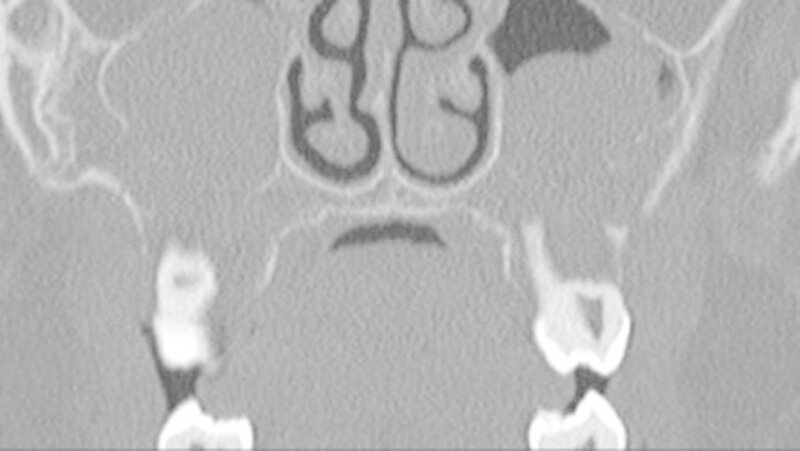

In der HR-CT zeigten sich Arrosionen am Oberkiefer und Kieferhöhlenboden sowie eine irreguläre Knochenbinnenstruktur mit Rarefizierung der Kochentrabekel und Demineralisation im Mittelgesichtsbereich, weiterhin eine Verschattung der Kieferhöhlen beidseits (Abbildungen 2 und 3).

Sonografisch fielen multiple pathologisch vergrößerte Lymphknoten am Hals beidseits auf. Dies bestätigte sich in der MRT, welche darüber hinaus eine Infiltration von Ober- und Unterkiefer, Schläfen- und Keilbein mit ossärer Destruktion und Knochen überschreitender Weichteilkomponente aufwies (Abbildung 4). Weitere Herde wurden im Schulterblatt, am Humerus-Kopf, sowie im Schlüsselbein, und an den Halswirbeln festgestellt.